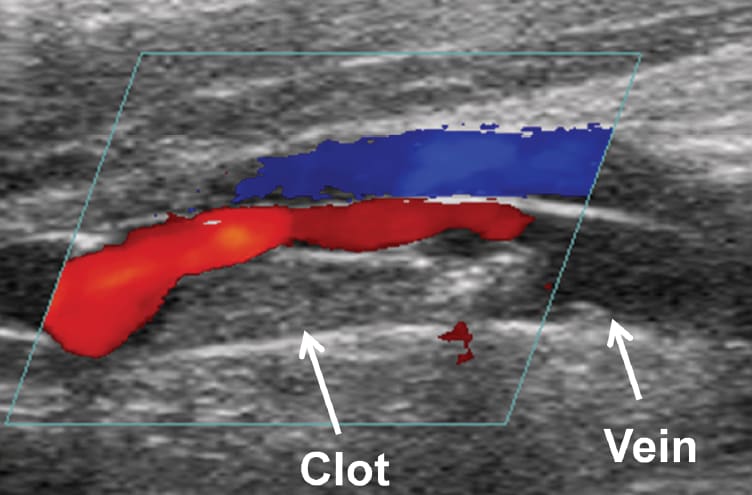

In the histotripsy system, an imaging transducer is closely aligned with the cloud-generating therapy transducer. This allows researchers to view microbubble cloud activity as it occurs. “We can see in real time when the cloud is generated, if it’s working, and if it has been effective in breaking up the clot,” says Xu. They also use color Doppler imaging to assess improvements in blood flow during the process.

A unique aspect of histotripsy is its influence on the cavitation process, which was previously considered uncontrollable. Xu and Maxwell achieve this precision using real-time cavitation monitoring and appropriate ultrasound pulse sequencing. The pulse sequence consists of a quick burst (less than 10 μs) of an ultrashort, high-pressure pulse. The pressures used to create cavitation are at least 10 times greater than pressures used in diagnostic ultrasound and comparable to pressure used in lithotripsy. “The idea is to generate the bubble cloud, fractionate a portion of the clot, and generate the seeds of the next cloud. All activity is finished before the next pulse arrives,” explains Xu.